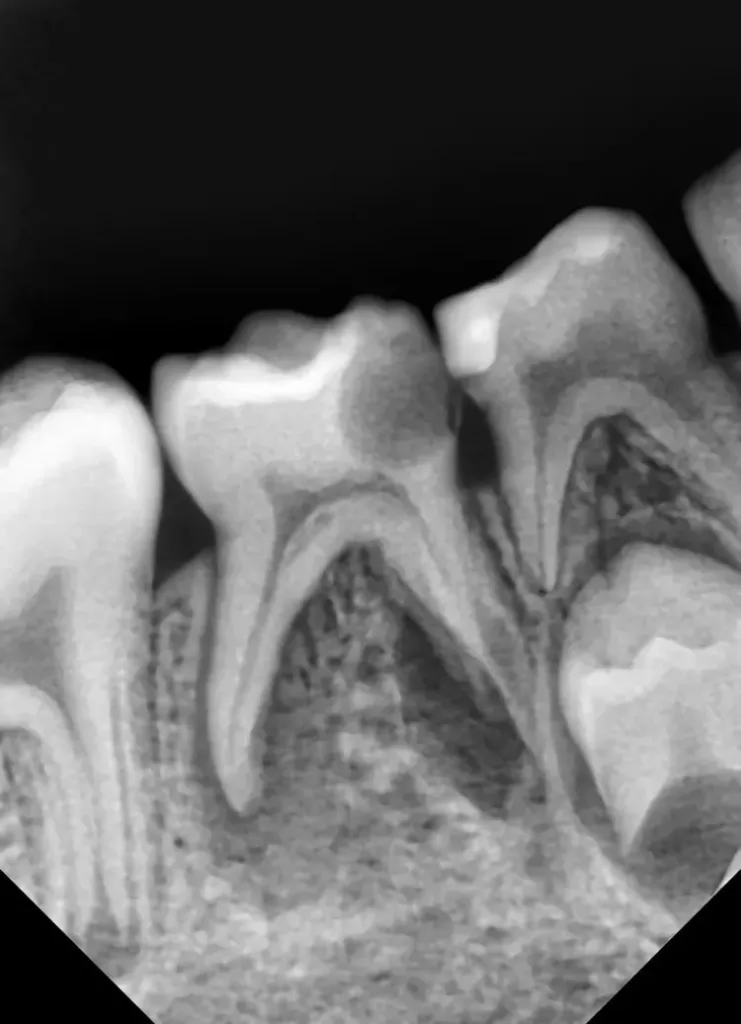

Als Ersatz für die inzwischen insuffiziente Kompositfüllung (Abb. 7) wurde mit dem Patienten und seinen Eltern eine definitive Versorgung mit einer konfektionierten Kinderzirkonkrone (NuSmile ZR Zirconia Posterior, USA) diskutiert und diese nach ihrer Einwilligung mit Fuji I (GC, Tokyo, Japan) eingesetzt (Abb. 8). Nach weiteren 3 und 6 Jahren wurden erneut Kontrollröntgenaufnahmen und klinische Bilder angefertigt (Abb. 9 bis 17). Dabei war auch die symmetrische Nichtanlage des unteren rechten 2. Prämolars zu beobachten (Abb. 11, 13 und 14).

Da am Zahn 85 die Diagnose „reversible Pulpitis“ gestellt wurde, erfolgte die Behandlung in Form einer klassischen Vitalerhaltung der Zahnpulpa mittels MTA (Rootdent, Technodent) und nachfolgender Kompositfüllung (Estelite ASTERIA, Tokuyama, Japan). So war es möglich, die Dynamik von Wurzelresorption nach Pulpotomie (Zahn 85) und Wurzelfüllung (Zahn 75) zu vergleichen. Nach 6 Jahren war kein Unterschied zwischen der Wurzelresorption des linken und rechten 2. Milchmolaren zu sehen (Abb. 11 und 12).

Bislang konnte keine weitere Progression der Wurzelresorption während des Beobachtungszeitraumes festgestellt werden. Der linke 2. Milchmolar zeigt eine geringgradige Infraokklusion (Abb. 12 und 15). Da der entsprechende Oberkieferprämolar adäquat durch die Randleiste des Nachbarzahnes abgestützt ist, ergibt sich zum jetzigen Zeitpunkt noch keine Gefahr einer ungewollten Elongation (Abb. 15 und 16).